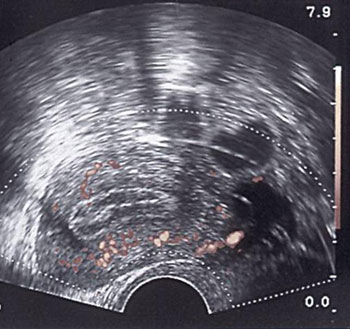

Εικόνα 8. Η ενδοωοθηκική

ροή αίματος την 6η, ή το πολύ την 7η ημέρα θεραπείας, είναι πλέον επαρκής, ώστε

να είναι δυνατή η καταγραφή της με τη μέθοδο Doppler, ενώ η απουσία της είναι

πρώιμος δείκτης πλημμελούς ανταπόκρισης. Αντίθετα, όπως εμφανίζεται στην εικόνα,

η πρώιμη εντόπιση των ενδοωοθηκικών νεόπλαστων αγγείων (πριν την 5η ημέρα θεραπείας),

με ιδιαίτερα χαμηλές αντιστάσεις (PI: 0,59 και RI:0,39), αποτελεί πρώιμο δείκτη

επικείμενης ωοθηκικής υπερδιέγερσης και ένδειξη για αναπροσαρμογή της θεραπείας.